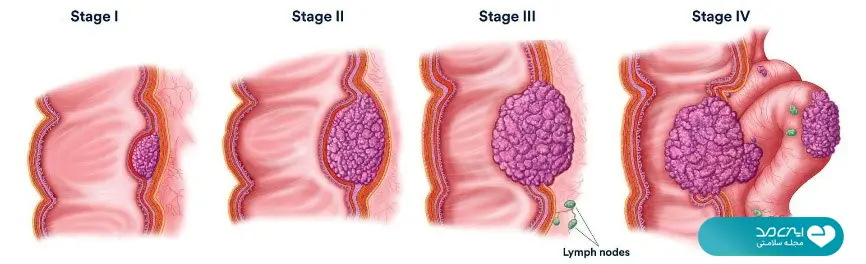

کاملترین راهنمای سرطان روده|علائم، علل، تشخیص و روشهای درمان

تایید شده توسط پزشکان متخصص ایزی مد محتوای این مقاله صرفا برای افزایش آگاهی شماست. قبل از هرگونه اقدام با پزشکان ایزی مد مشورت کنید عنوان موضوعات این صفحه سرطان روده بزرگ مانند همه سرطانها برای بسیاری یادآور ترس و ناامیدی است. اما بخش زیادی…

صفر تا صد درمان سرطان روده؛ از جراحی و شیمی درمانی تا روشهای نوین پزشکی

تایید شده توسط پزشکان متخصص ایزی مد محتوای این مقاله صرفا برای افزایش آگاهی شماست. قبل از هرگونه اقدام با پزشکان ایزی مد مشورت کنید عنوان موضوعات این صفحه روشهای درمان سرطان روده بزرگ در سالهای اخیر با پیشرفتهای پزشکی متحول شدهاند و همین موضوع…